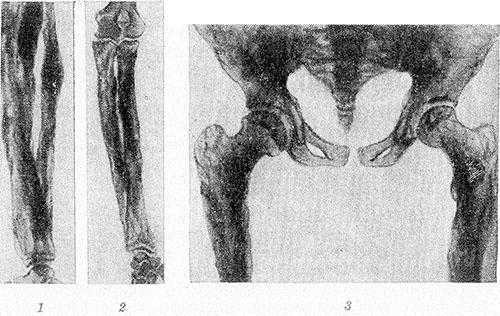

Рис. 1. Больной системным гиперостозом: характерный вид длинных утолщенных бедер цилиндрической формы, саблевидных голеней, сгибательных контрактур в крупных суставах.

Ранний период жизни больного ребенка характеризуется замедленным развитием, небольшой прибавкой в весе, гипотрофией мышц конечностей. Ходить такие дети начинают на 3— 4-м году жизни. В дальнейшем наблюдается прогрессирующая мышечная слабость и развитие так наз. утиной походки. При тщательном осмотре можно обнаружить утолщение конечностей, приобретающих цилиндрическую форму без выпуклостей и углублений; суставы почти не выделяются (рисунок 1). Кожа над утолщенными костями натянута, отмечается уменьшение объема мышц (инволютивная Миопатия). Постоянным симптомом являются локализующиеся в диафизах больших трубчатых костей интенсивные, ноющие, «грызущие» боли, обычно связанные с периодом активации болезни и усиливающиеся при физ. нагрузке, тутоподвижность суставов и скованность движений. Описаны случаи непропорционального роста больных с выраженным удлинением конечностей, нарушением сухожильных рефлексов. Редко может развиться глухота и парез лицевого нерва по периферическому типу. Изменений крови и эндокринных органов обычно нет, однако М. В. Волков в 1974 г. сообщил о больной 19 лет, у к-рой были обнаружены инфантилизм, резкая гипоплазия гениталий и отсутствие менструаций, гипопластический субнанизм с отставанием умственного развития.

Рис. 2. Рентгенограммы костей голени (1), предплечья (2), таза и верхней трети бедер (3) больного системным гиперостозом: длинные трубчатые кости цилиндрически и булавовидно утолщены, корковый слой неплотный, резко утолщенный, имеет неравномерную пятнистую структуру с неровными контурами; кости таза утолщены.

Рентгенологически определяется симметричный гиперостоз трубчатых костей скелета. Пораженные кости громоздки, их диафизы утолщены в 2—3 раза, костно-мозговой канал равномерно сужен, но никогда не исчезает полностью. Эпифизы не изменены. Корковый слой значительно утолщен кнаружи и кнутри, с явлениями остеосклероза, но структура его не нарушена. Рисунок губчатого вещества изменен — костные балки грубы, толсты, плотны и обрывисты (рис. 2). В детском возрасте структурный рисунок может быть неравномерным, иметь рассеянный крупнопятнистый очаговый характер.